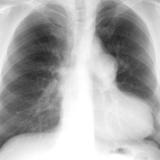

ASD 2 PA